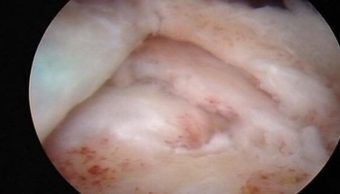

Durante la artroscopía se demuestra una ruptura de la inserción del tendón del supraespinoso en la cabeza del húmero (troquiter)